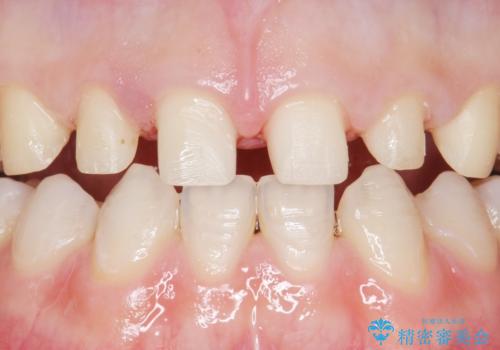

- K-POP(Kポップ)アイドルのような歯にしたいと希望され来院された患者様です。

矯正を途中でやめてしまったとのことで、歯に矯正の接着材が残っており着色も顕著でした。

奥歯の咬合面にはレジンが盛られた状態でした。

見た目と咬み合わせを改善するため、セラミッククラウンによる治療を行いました。